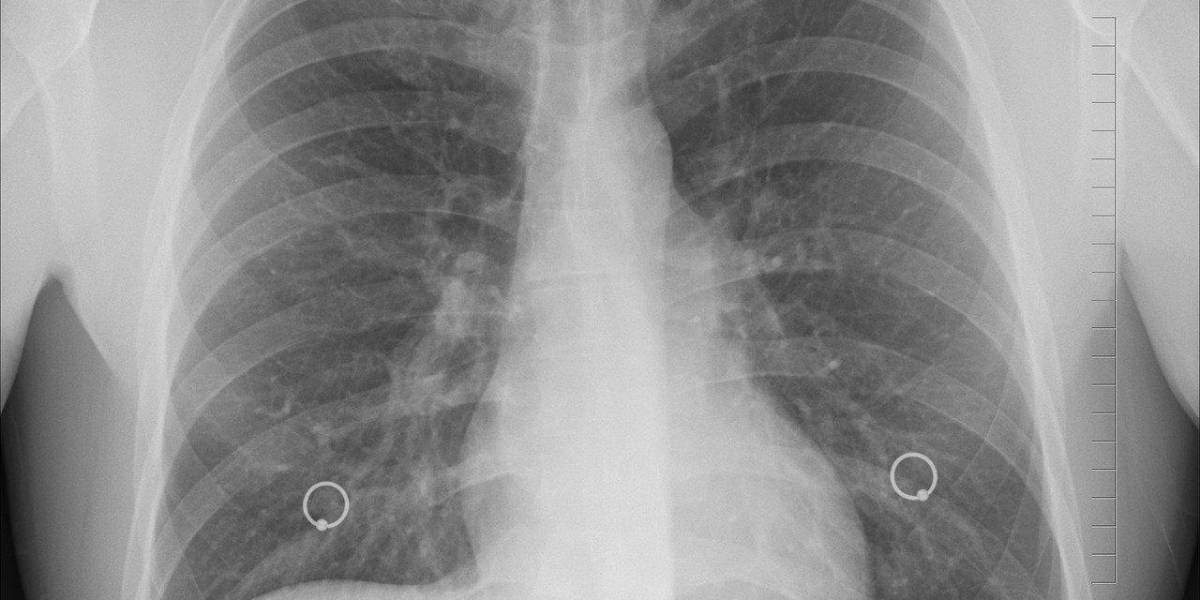

La bacteria no se transmite de persona a persona, sino que lo hace por vía inhalatoria o a través del agua. Provoca fiebre e infección pulmonar

Afirmó que la bacteria no se transmite de persona a persona, sino que lo hace por vía inhalatoria o a través del agua. Provoca fiebre e infección pulmonar y fue identificada tras estudios del Instituto Malbrán, referente nacional en infectología.

Los ocho nuevos pacientes fueron incorporados al registro al ampliar el criterio de inclusión, a partir de que se conoció que la bacteria causante no siempre produce neumonía bilateral. Se contabilizan 19 contagios hasta la fecha.

La semana pasada una serie de decesos por una neumonía bilateral agresiva habían alertado a las autoridades sanitarias, que tras primeros análisis descartaron que se tratara de covid-19, gripe, influenza o hantavirus.